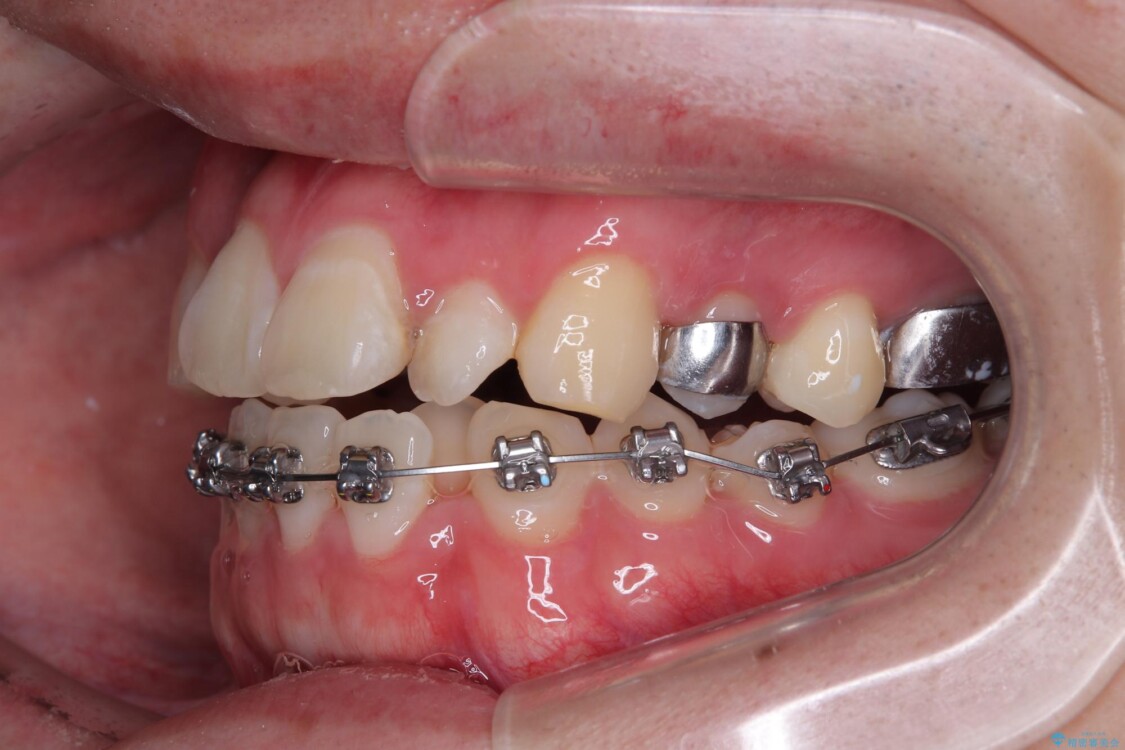

治療方針

このような歯列の狭さに起因するデコボコを改善するために、**MARPE(骨に固定する上顎急速拡大装置)**を使用して、上顎の横幅を拡大し、これにより歯が並ぶためのスペースを確保し、メタルブラケットを用いて歯列を整えていく計画としました。

費用面を考慮し、装置はコストパフォーマンスに優れたメタルブラケットを選択。見た目よりも機能と効果を重視したい方には特におすすめの選択肢です。

治療途中

• 1年でここまで変わる!歯列のがたつきと正中のズレを改善した矯正治療(メタルブラケット×MARPE) 治療途中画像